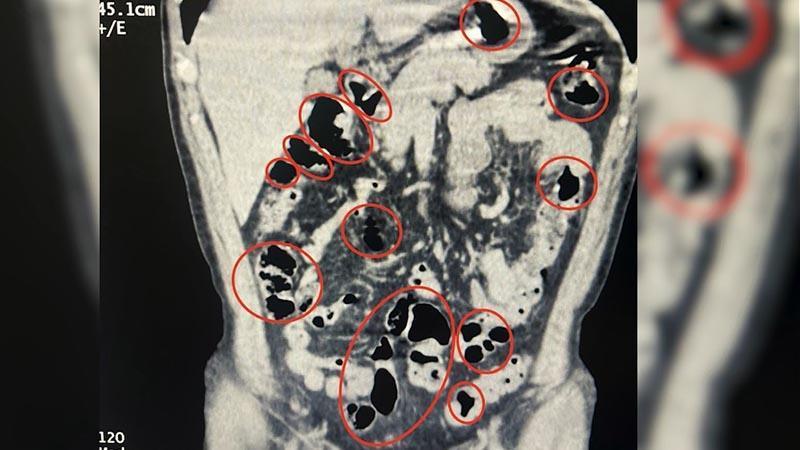

İl Emniyet Müdürlüğü Narkotik Suçlarla Mücadele Şube Müdürlüğü ile İstihbarat Şube Müdürlüğü ekiplerinin çalışması sonucu Tatvan ilçe girişinde durdurulan bir yolcu otobüsünde seyahat eden yabancı uyruklu 2 kişinin üzerinde arama yapıldı. Aramalarda şüphelilerin üzerinde 36 kapsül içerisinde uyuşturucu ele geçirildi. Tatvan Devlet Hastanesi’ne götürülen şüphelilerin burada yapılan röntgen ve tomografi incelemelerinde de mide ve bağırsaklarında yabancı cisimler tespit edildi. Tıbbi müdahale sonucu şüphelilerin yuttuğu 14 kapsül çıkarıldı. Toplam 50 kapsül halinde 385 gram metamfetamin ele geçirilen 2 şüpheli gözaltına alındı.